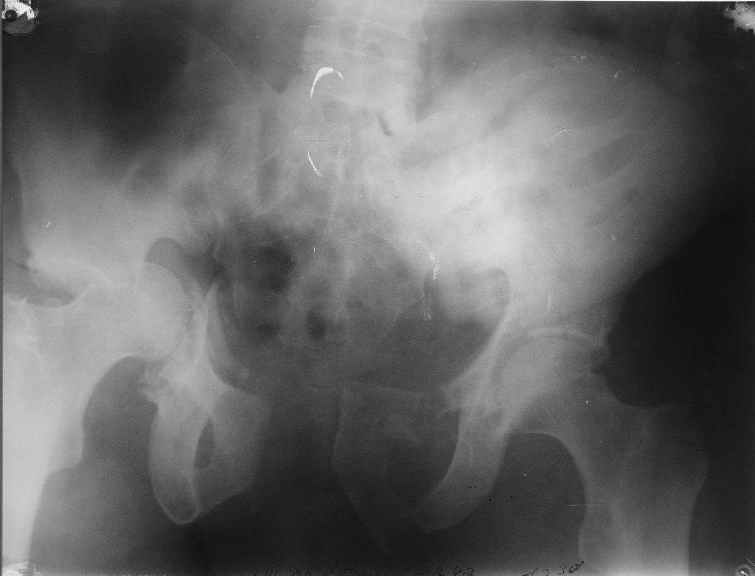

Уважаемый Антон, у Вашего больного имеется транстектальный поперечный перелом вертлужной впадины с переломом заднего края, перелом заднего типа, подвздошный вывих, возможна импрессия и повреждение нерва. Головка при этих повреждениях в нагружаемой части должна быть целой.

Высылаю нечто подобное, аппарат пусть не смущает, просто больного оперировал через 2 месяца после травмы, а у него еще полный разрыв кп сочленения с контрлатеральной стороны.